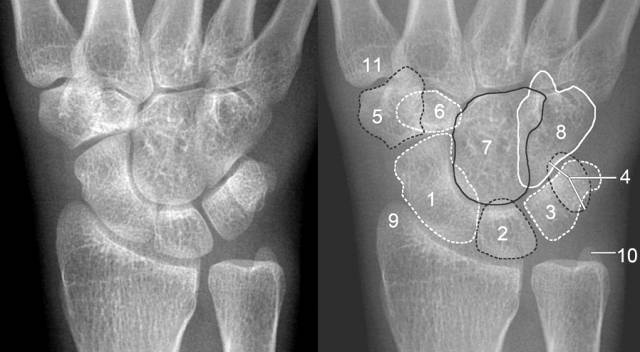

( 1)正位片上:前后排腕骨后缘形成光滑的弧线;前后排腕骨不重叠;头、钩、月、三角骨间形成十字间隙。月骨于正位片上为楔形、侧位片上为月牙形,窝状关节面朝前、且与头状骨紧贴。

1.舟骨 2.月骨 3.三角骨 4.豆状骨 5.大多角骨 6.小多角骨 7.头状骨 8.钩骨 9.桡骨茎突 10.尺骨茎突 11.第一掌骨基部